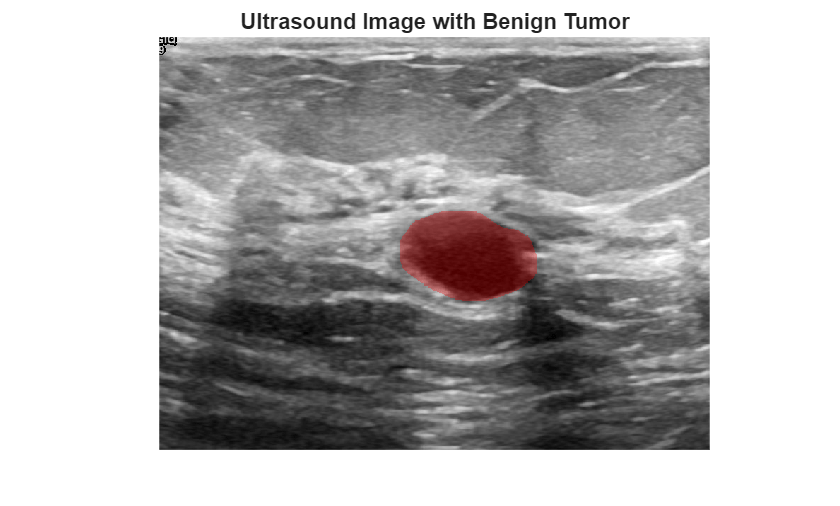

Tune separate fuzzy inference systems to classify pixels based on color and

texture, and combine these systems into a fuzzy tree for image

segmentation.